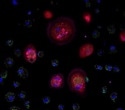

Several techniques, including low-resolution transcriptome profiling via NanoString DSP, spatial transcriptomics via 10x Genomics Visium technology, whole-slide imaging, and single-cell image analysis via the StrataQuest software from TissueGnostics, helped analyze the spatial distribution of IDO1 and PDL1 in the skin tissue of patients with cutaneous leishmaniasis.

Researchers investigated the location and expression of IDO1 and PDL1 within the tissue samples. Multiplexed imaging and transcriptome profiling afforded them useful insights into the distribution of these immune checkpoints within the skin lesions.

The study found that infected macrophages express IDO1 and PDL1. This analysis was performed using the StrataQuest image analysis software and showed a positive correlation between the expression of IDO1 and PDL1 and the amastigote burden, which can be understood as representing the parasite load.